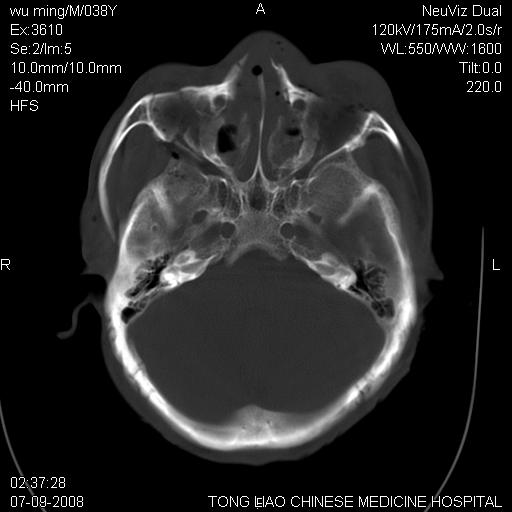

颅底多发骨折。

颅底多发骨折.

颅底多发骨折.上颌骨多发骨折

右侧眼眶,上颌骨,鼻骨、上颌窦等很多

考虑:面骨、颅底骨多发骨折,颅内高压(脑肿胀)。

面骨、颅底骨多发骨折,右侧硬膜下小血肿,弥漫轴索损伤,死亡原因可能是多种因素致。

1)颅底骨及颌面骨多发性骨折。2)副鼻窦及双侧鼻腔积血。

颅底骨折,窦腔内积血。考虑死亡原因为脑水肿压迫脑干或因大量失血死亡。

前颅窝颅底骨折,死的原因应该从头部来看不用说就是重度颅脑损伤。

颅底、上颌骨,双侧颧骨多发骨折。死因或许与此无关,是否有腹部脏器损伤有关